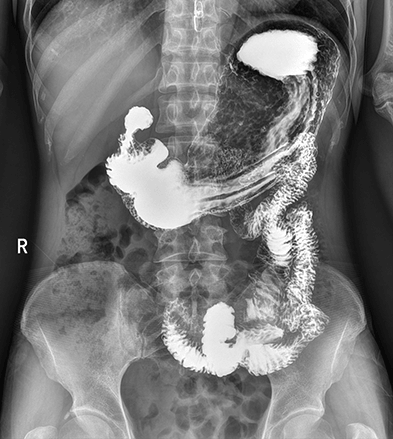

平板探测器

超大尺寸

超范围

高清点片

DFP

同步曝光